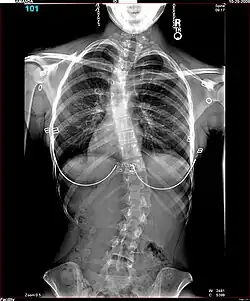

Polio patients would sometimes develop scoliosis, a condition where the spine becomes curved laterally (from side to side).[5] Harrington realised that existing treatments for scoliosis, which relied heavily on physical therapy, were inappropriate for patients paralysed by polio, and began to research new treatments. An early method he tried for scoliotic polio patients was manual correction of the scoliotic deformity at the time of surgery, and internal fixation of each facet. There were some benefits to this treatment but Harrington found that the fixation would not hold.[4] The hooks and threaded rods used would corrode and break, causing curvature to return to the spine. Two patients of this procedure died.[5]

The Harrington Rod, or Harrington implant, is a device for the straightening of the spine inside the body, designed by Paul Harrington. The device consists of a stainless steel rod, attached to the spine at the top and bottom of the curve with hooks. Attached ratchets are then tightened to distract or straighten the spine. Following surgery to insert the rod, the patient wears a postoperative plaster cast or brace for a few months, until vertebral fusion has occurred, after which the cast or brace is removed.[5]

The major drawback of the Harrington Rod is that it straightens out the normal front to back curvature of the segment of the spine that is fused, which in many patients results in a flat back deformity, also known as "flatback syndrome". Advances in surgical techniques and technology in the late 1990s were eventually able, in most cases, to correct scoliosis without causing flatback syndrome, leading to the gradual phasing out of the Harrington Rod.[6]